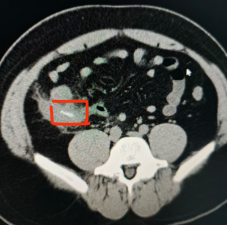

据综合外科接诊医生介绍,患者因持续性腹痛就诊,经影像学检查和术中探查发现,竟是一块鸡爪骨头嵌入阑尾腔内!还造成阑尾穿孔!腹腔内出现明显炎症反应!手术团队迅速开展微创术式,成功取出骨头并切除病变阑尾,患者术后恢复良好。